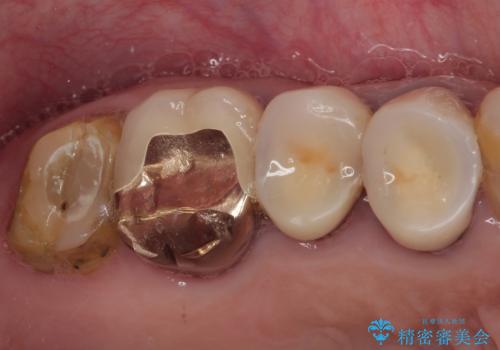

- 神経を抜く処置の後に装着した詰め物が外れてしまったとのことで来院された患者様です。

患者様自身、当院の症例をご覧になり、神経の取り除かれた歯はクラウンを装着するべきと理解していただいていたため、詰め物の捕れた歯とその後ろの歯の2本を補綴治療することとしました。

根管治療の提案をしましたが、今回は取り急ぎ補綴治療のみを希望されました。